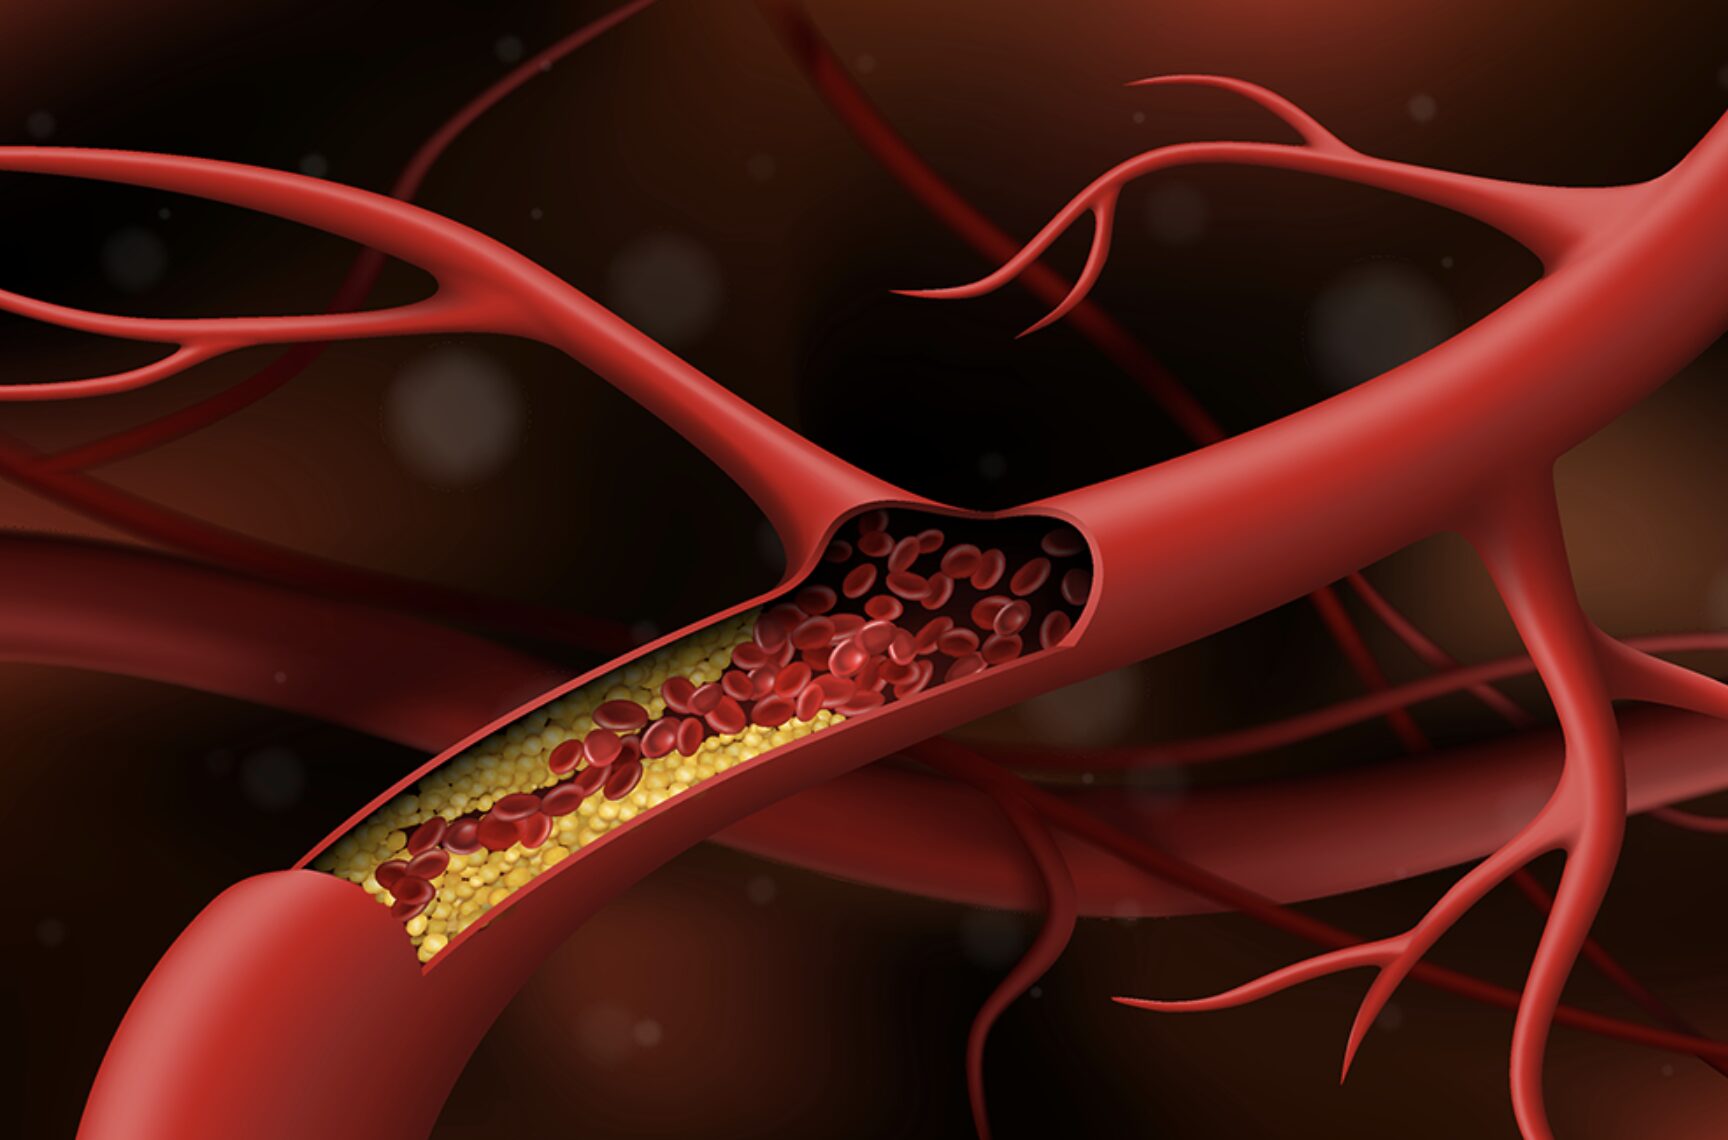

Một cụ ông 65 tuổi (ở Đồng Tháp) bị đau dữ dội vùng thắt lưng và hai chân đến mức không thể đi lại, đứng trước nguy cơ đoạn chi. Gia đình đã đưa ông đi khám nhiều nơi nhưng chưa an tâm, sau cùng chuyển đến Bệnh viện Đa khoa Quốc tế S.I.S Cần Thơ, nơi ông được điều trị và phẫu thuật thành công, giữ lại được đôi chân.

Nhập viện trong tình trạng chân trái tím tái, sưng phù một cách bất thường, không thể tự di chuyển, nữ bệnh nhân 57 tuổi suýt phải đoạn chi. Rất may, bà được bệnh viện Đa khoa Quốc tế S.I.S Cần Thơ can thiệp tái thông tĩnh mạch chi thành công.